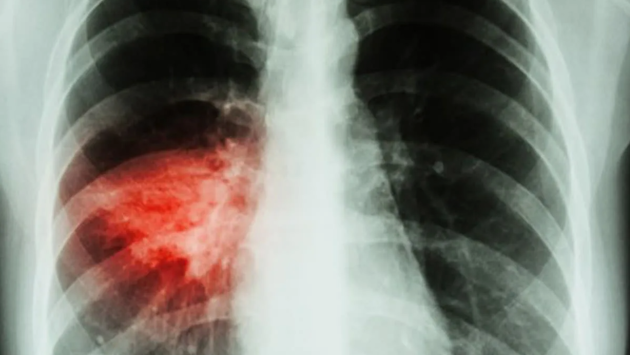

В Тюменской области зафиксирован резкий рост внебольничных пневмоний

Последние две недели в Тюменской области наблюдается тревожная тенденция - резкий рост случаев внебольничной пневмонии. По данным областного управления Роспотребнадзора, этот показатель достиг 63 на 100 тыс. населения. Ситуация осложняется сезонным ростом заболеваемости ОРВИ и коронавирусом, что, по мнению специалистов, связано с началом учебного года и формированием детских и трудовых коллективов.